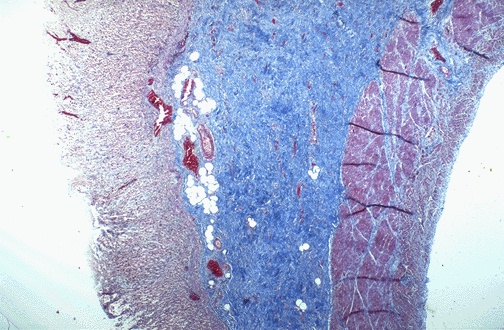

Esophageal motility problems can occur in patients with progressive systemic sclerosis (scleroderma) because the submucosa becomes fibrotic. This occurs most often in the esophagus, but may also be seen elsewhere in the GI tract. Here in the stomach, a trichrome stain demonstrates a blue submucosa because of the extensive fibrosis. |